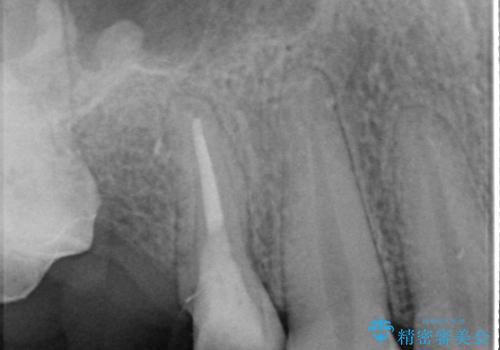

右上のブリッジが途中で切断されて、手前の歯が根の治療の途中でした。

根の治療を行いその後にオールセラミックブリッジを装着する計画となりました。